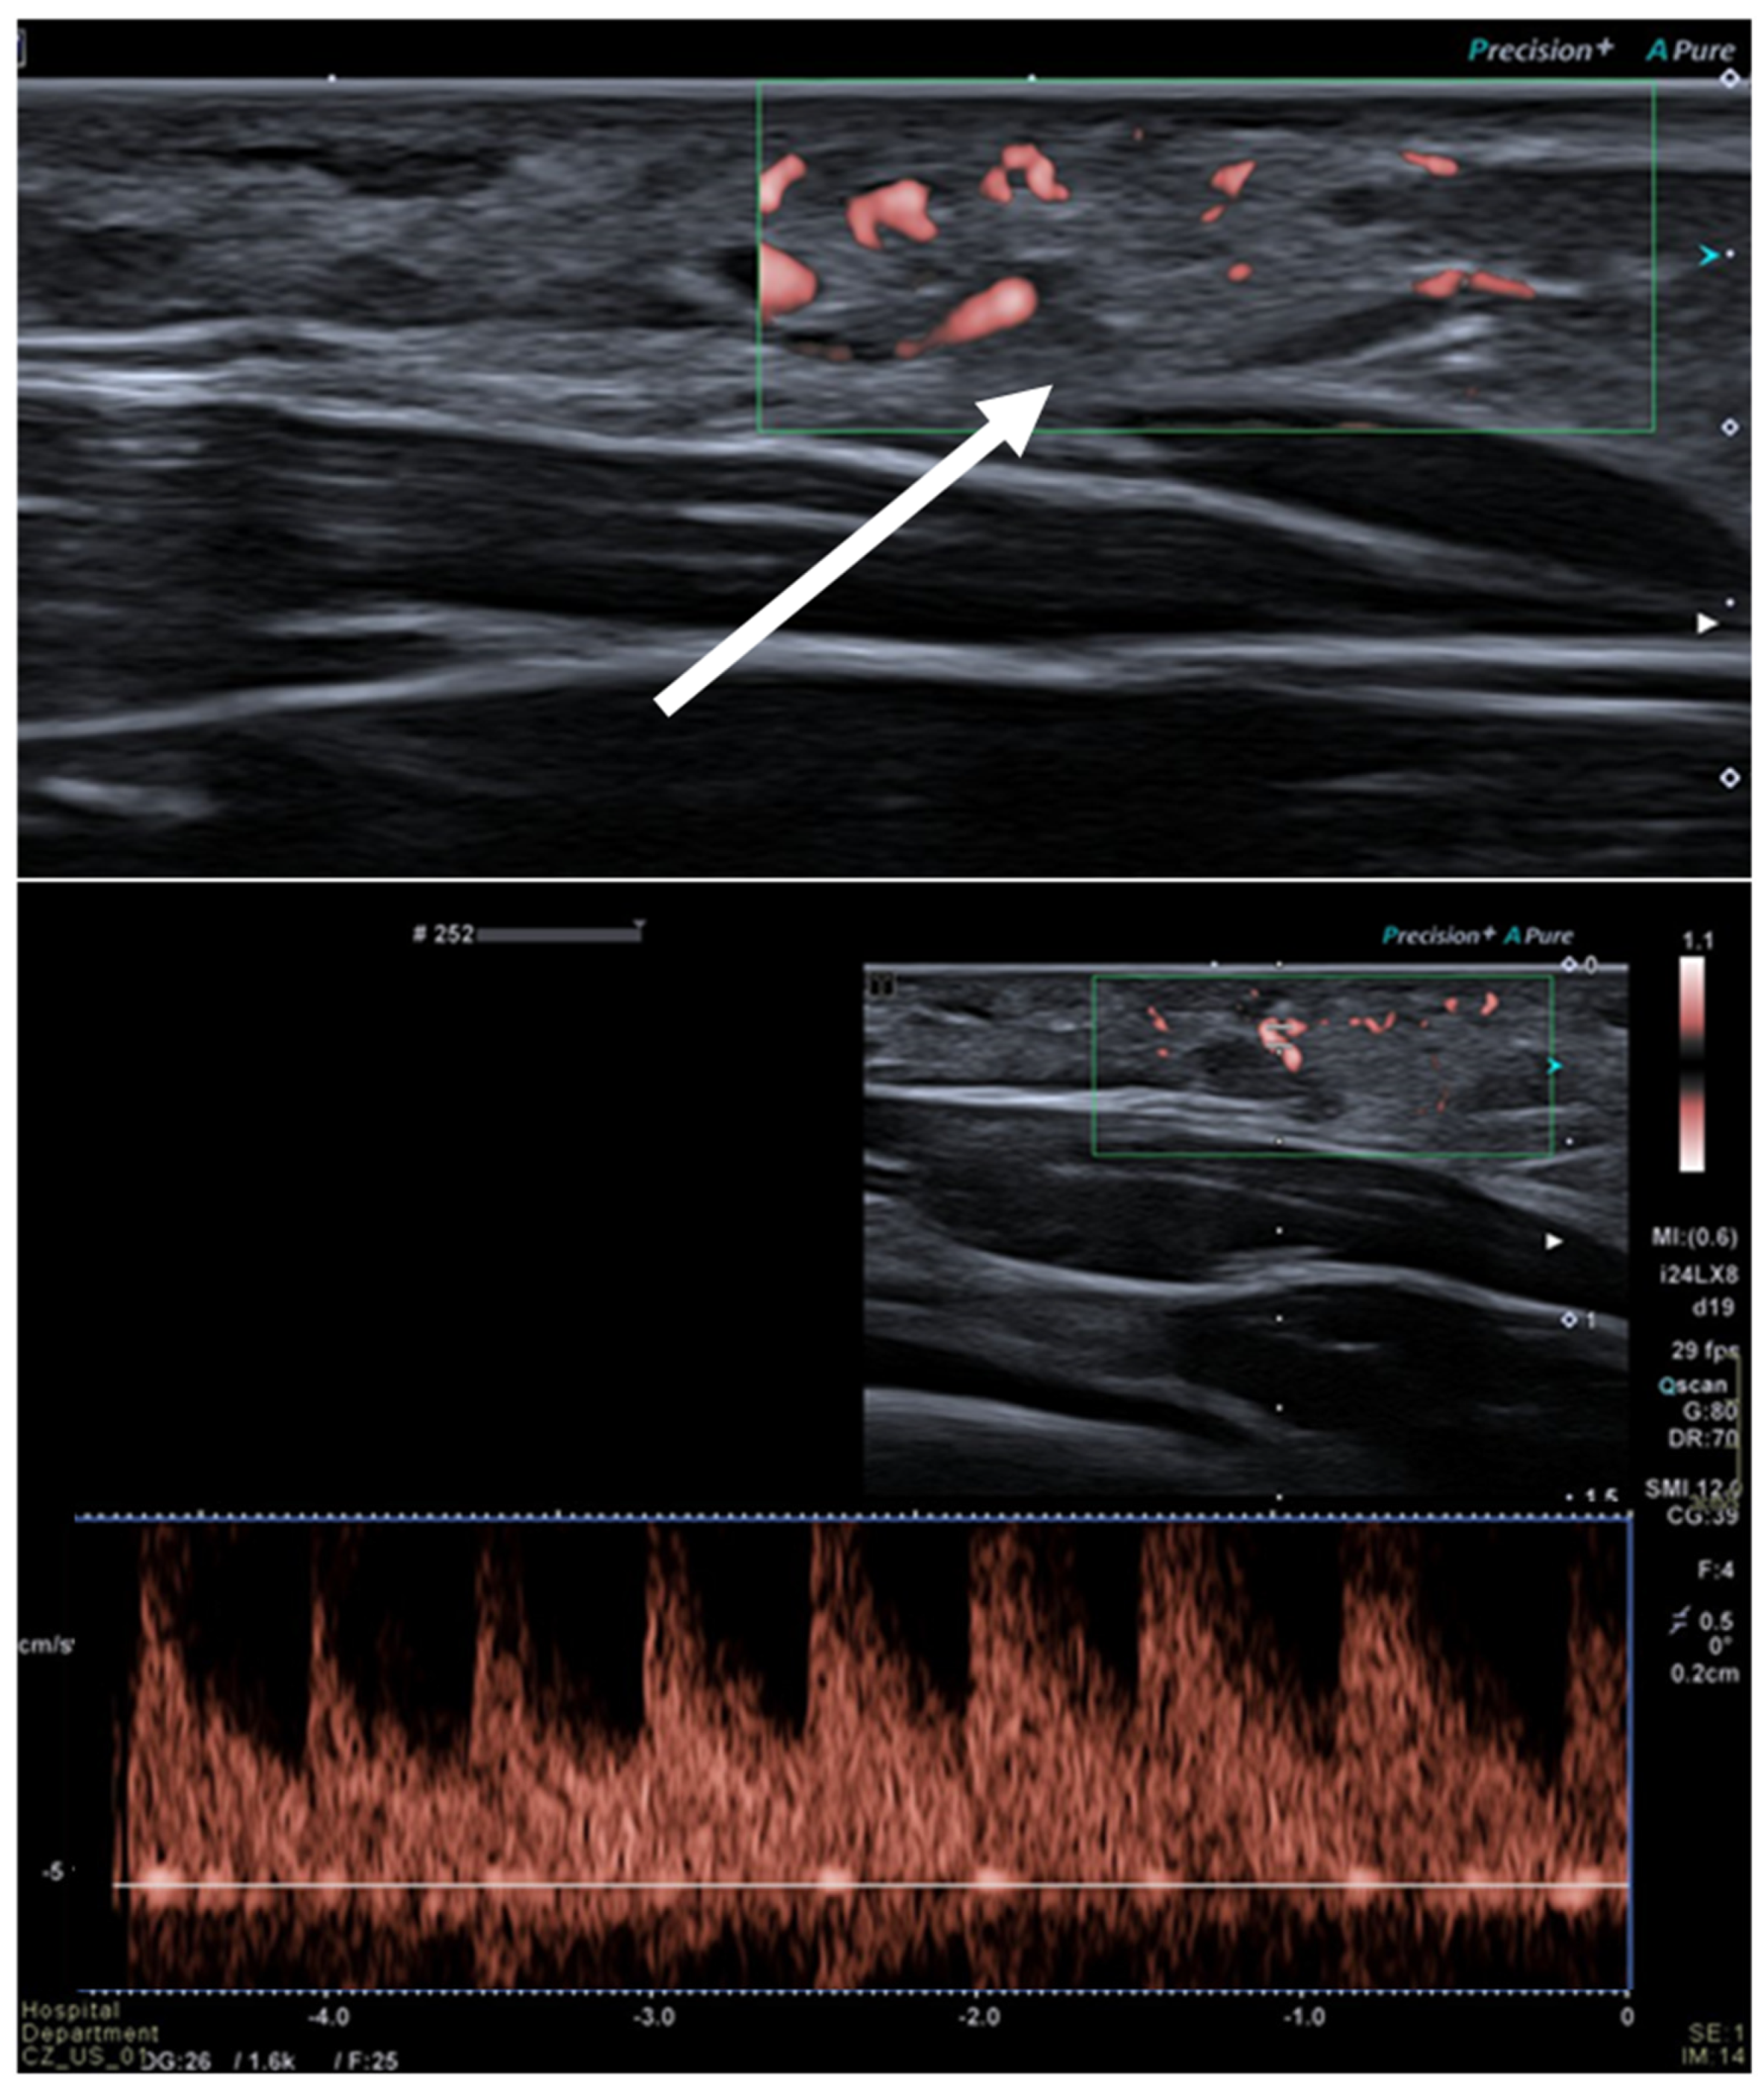

2.3. Hemangioma